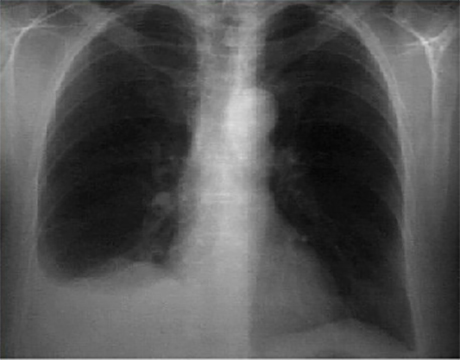

This chest X ray shows a pleural effusion.

In this PA view, it is demonstrated by a radiopaque shadow at the right lung base with a curvilinear superior border that obliterates the right costophrenic angle. The left lung field is clear. There is a normal cardiac silhouette and heart size, as demonstrated by the normal cardiothoracic ratio.

The pulmonary vascularity, mediastinum and hilar areas are normal.